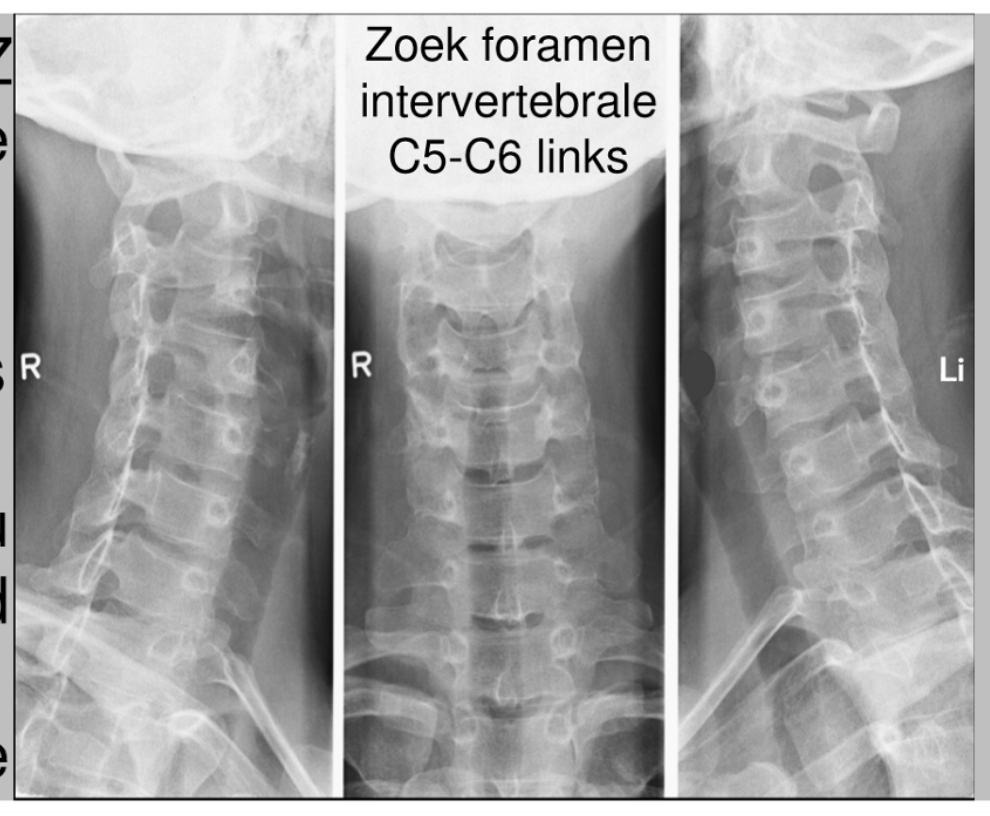

formamina intervertebrale

hier komen de spinale zenuwen uit

schuine opname = oblique view

foramen intervertebrale C4-C5 (links)

daaruit komt spinale zenuw C5

processus uncinatus (linker)

pedikel (linker)